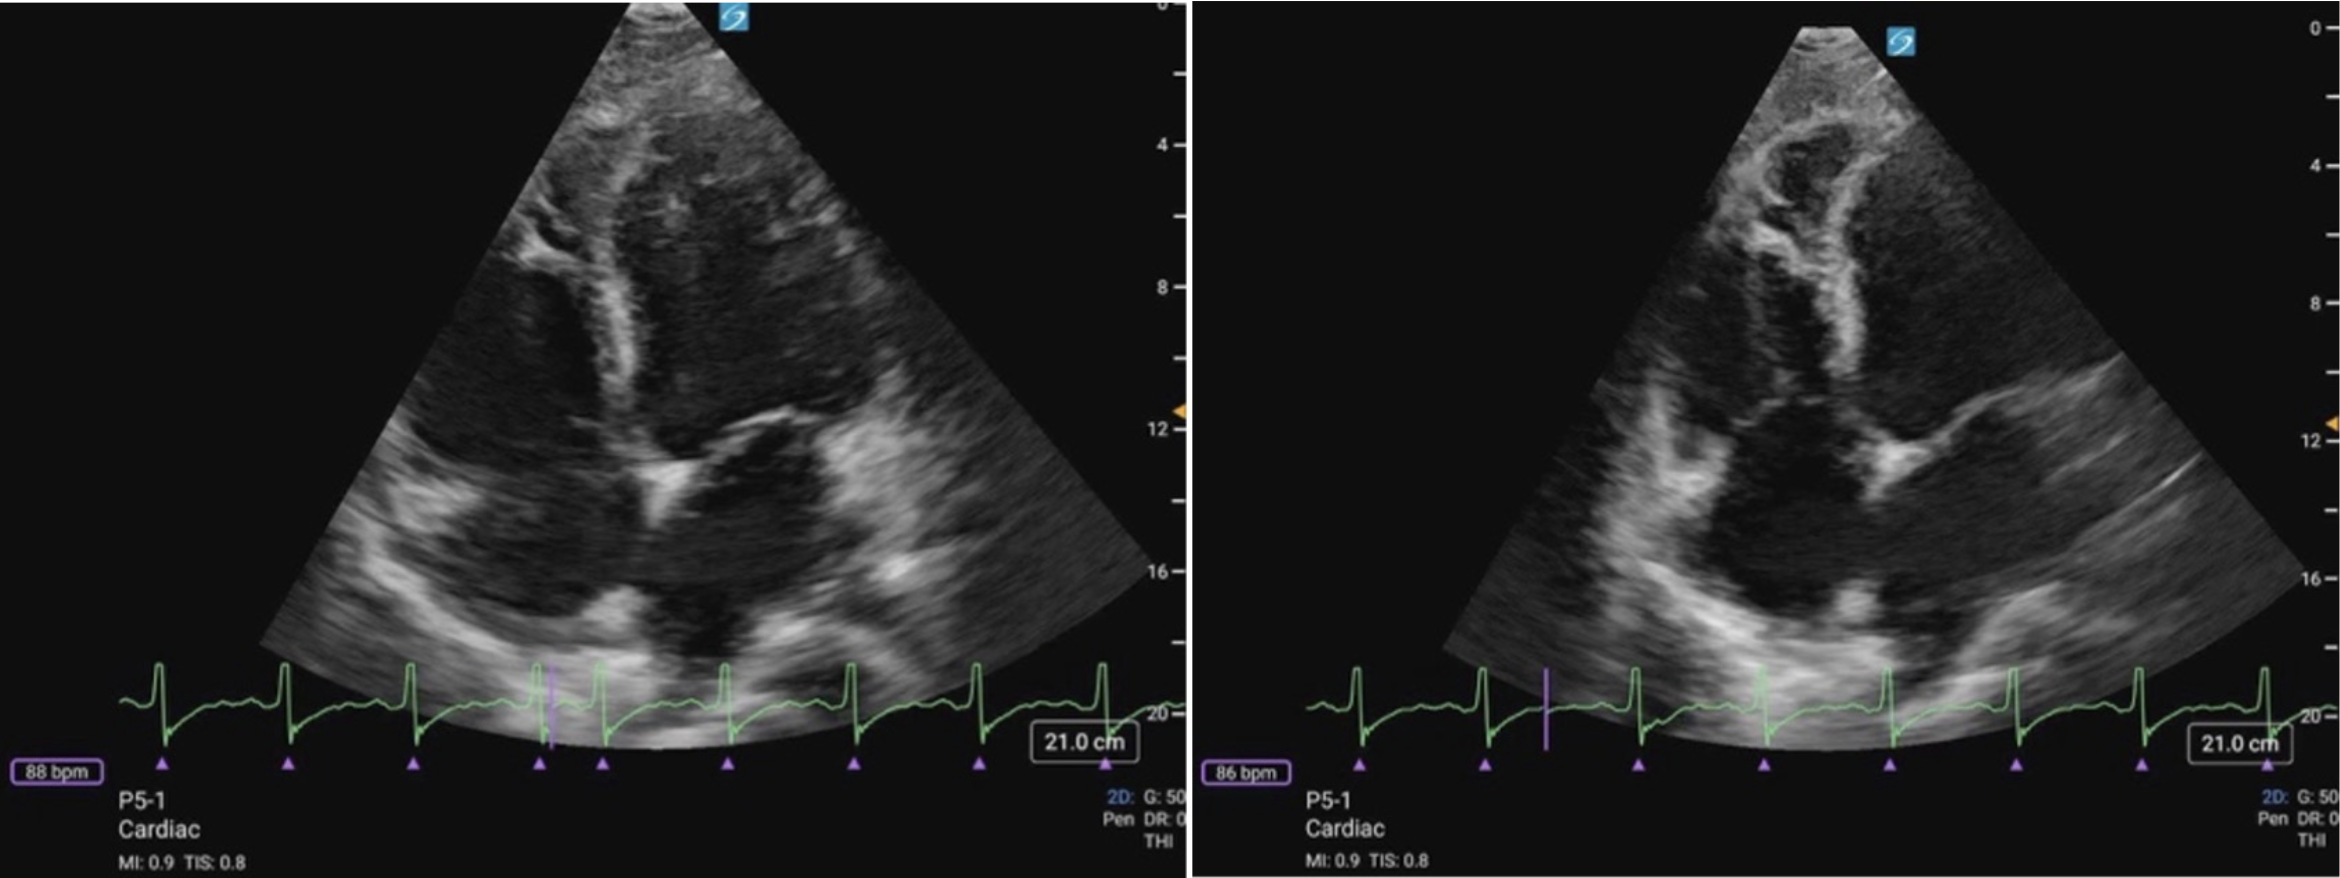

Figure 1ab: LV levels in the PLAX view (a) and A4C (b) in cardiology convention

Each cardiac view offers a different perspective of the LV, displaying various walls and myocardial segments. The LV is typically divided into three levels: basal, mid, and apical. The basal segments are located closest to the atrioventricular valves and represent the upper portion of the LV; the mid segments are situated in the middle, at or around the level of the papillary muscles, and the apical segments are near the apex of the ventricle. Understanding which walls are visualized in each view is key to assessing LVfx.